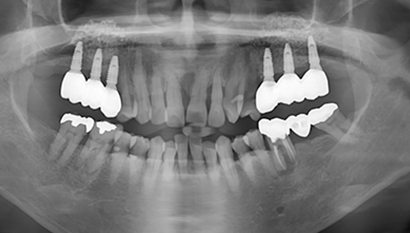

W Dental Clinic Before & After

治療前後の写真

Before

After